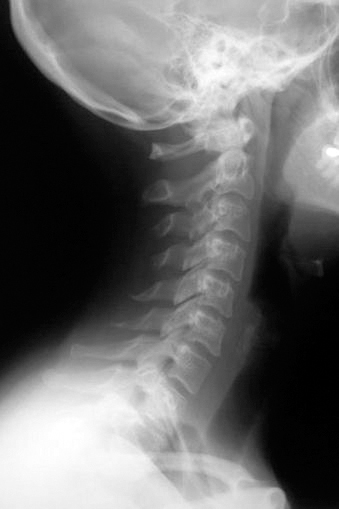

Так что шейный отдел позвоночника, состоящий из семи позвонков, должен иметь достаточную длину и определенную статику (рис. 1).

Рис. 1. Нормальная статика шеи. Правильный физиологический изгиб: А=А1

А что в действительности имеем мы? Даже здоровый позвоночник (хотя где его найдешь?) с возрастом деформируется, «проседает», меняет статику. Появляется симптом смещенной вперед и запрокинутой назад головы (рис. 2).

Рис. 2. Гиперлордоз шейного отдела позвоночника: B > B1

В результате небольшой физиологический изгиб гипертрофируется, и шейные позвонки «проваливаются» вглубь шеи. Особенно интенсивно это происходит при «сидячей» работе. Формируется гиперлордоз шейного отдела позвоночника. Чаще всего виной тому становится не возраст, не тяжесть гравитации, а попросту плохая осанка. При сутулости попытка смотреть в глаза собеседника достигается запрокидиванием головы назад, сопровождающимся взглядом исподлобья. Бывает, посмотришь на женщину – лицо еще молодое, видно, что она ухаживает за собой. А взглянешь издали – прямо старушка ковыляет: ссутулилась, шейка вперед подалась, плечики сжались. Хорошо, сама себя не видит, а то бы очень огорчилась.